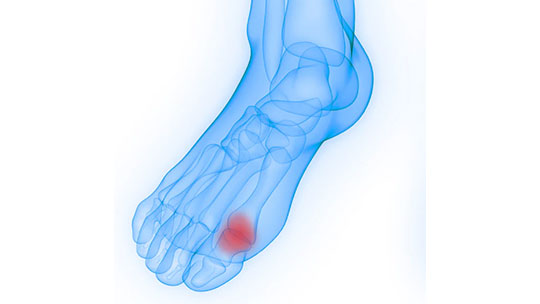

Hallux Limitus Rigidus

Hallux Limitus and Hallux Rigidus involve the joint that is located at the base of the big toe and causes pain and stiffness in the big toe. Being a progressive condition, the toe will become increasingly harder to bend over time.

Hallux refers to the big toe. Limitus refers to a decrease in motion of the joint (the early stage) and Rigidus referes to a joint that is rigid with very little to no movement (the later stage).

Hallux Rigidius is actually a form of degenerative arthritis.